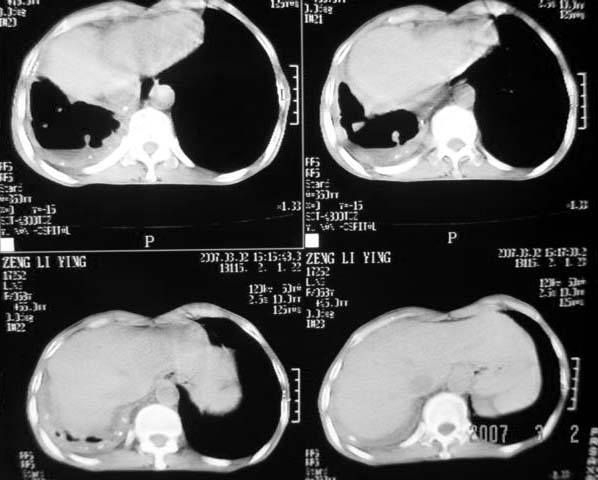

以下是引用dyqct在2007-3-2 22:04:00的发言:[br]考虑:1、右侧毁损肺伴支气管胸膜瘘(多条支气管与胸腔相通、液气胸);[br] 2、左肺浸润型肺结核。[br][br][br][br]